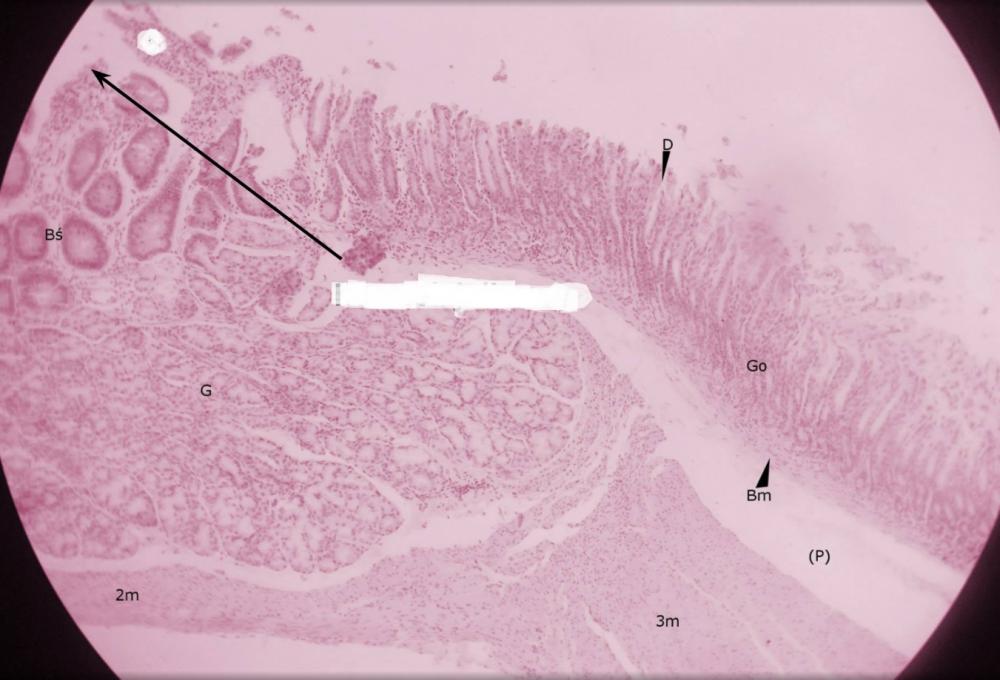

dołki żołądkowe (przejście żołądka w dwunastnicę)

pólka żołądkowe (przejście żołądka w dwunastnicę)

rozgałęzione gruczoły cewkowe - odźwiernikowe (przejście żołądka w dwunastnicę)

kosmek jelitowy (przejście żołądka w dwunastnicę)

krypta jelitowa (przejście żołądka w dwunastnicę)

gruczoły Brunnera (przejście żołądka w dwunastnicę)

błona mięśniowa, składająca się z warstwy okrężnej o podłużnej (przejście żołądka w dwunastnicę)

miejsce po błonie podśluzowej (przejście żołądka w dwunastnicę)

blaszka mięśniowa błony śluzowej (przejście żołądka w dwunastnicę)

gruba, trójwarstwowa mięśniówka żołądka (przejście żołądka w dwunastnicę)